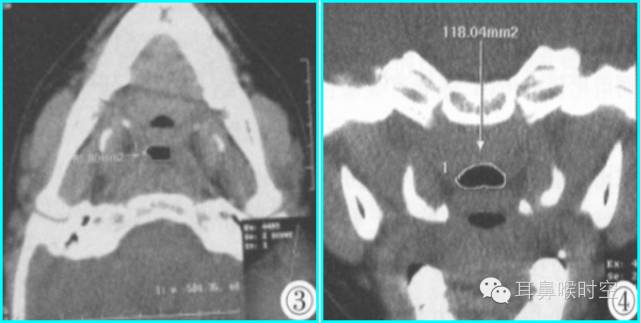

②冠状面:输入小标题

测量层面:以通过蝶-枕结合层面的冠扫作为之,选择腺样体最大截面及上、下相邻层面等3个层面测量(图1,2) , 并求出平均值

正中矢状面测量:

腺样体厚度与鼻咽气腔前后径的比值

鼻咽气腔有效气道的前后径大小

鼻咽气腔有效面积。

图1 鼻咽气腔N值 图2 腺样体A值

③同层动态CINE:

利用GE公司HispeedAW工作站,选择任意3个层面测量(图3,4)

求两两之间的面积最大差值(△S=118.04- 91.15) 。

图3 鼻咽气腔有效面积 Sn 图4 CINE测量有效面积 Sn1